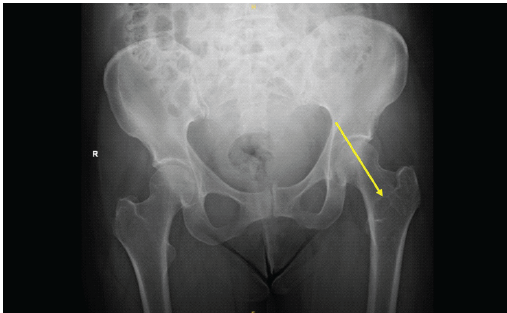

A 64-year-old female presented following a mechanical fall at work, reporting bilateral hip pain, more pronounced on the left side. The patient had no history of hip pain before the fall. Clinical examination demonstrated a preserved range of motion in both hips, with discomfort on weight bearing but no focal neurological deficit. Initial anteroposterior pelvic radiography demonstrated no acute fracture, but revealed a well-defined lucent lesion in the proximal left femur (Fig. 1). A computed tomography (CT) scan of the pelvis was subsequently performed to exclude an occult fracture. CT confirmed an elongated intramedullary lucent lesion within the proximal left femoral metaphysis, characterized by sclerotic margins without cortical destruction, endosteal scalloping, or an associated soft-tissue mass, suggesting a non-aggressive process (Fig. 2 and 3).

Figure 1: Anteroposterior pelvic radiograph demonstrating a well-defined lucent lesion in the proximal left femoral metaphysis (arrow), with no associated fracture.